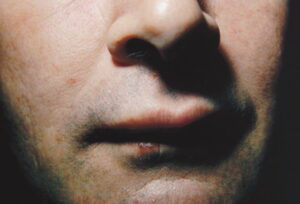

Angioedema is the swelling of deep dermis, subcutaneous or submucosal tissue due to vascular leakage.1 It was first described in 1586.2 Other terms, such as giant urticaria,3 Quincke edema,4 and angioneurotic edema,5 have also been used in the past to describe this condition. Clinically, angioedema is usually nonpitting and nonpruritic. The area of involvement is often skin-colored or slightly erythematous. Depending on the area of swelling, pain can be absent or mild, as in most peripheral or facial swelling, or can be very severe, as in gastrointestinal angioedema. Laryngeal swelling is life-threatening. It should be treated as a medical emergency.

Patients usually describe swelling of the face (eg, eyelids, lips), tongue, hands, and feet. It can be acute or chronic, and each episode of angioedema may last a few hours to a few days. A local burning sensation and pain can be observed without pronounced itchiness or local erythema. Abdominal pain can sometimes be the only presenting symptom of angioedema. Throat tightness, voice changes, and trouble breathing may indicate airway involvement.

For skin involvement, examination can easily identify areas of swelling with or without erythematous skin, often with ill-defined margins. Some cases of angioedema occur in patients with urticaria.